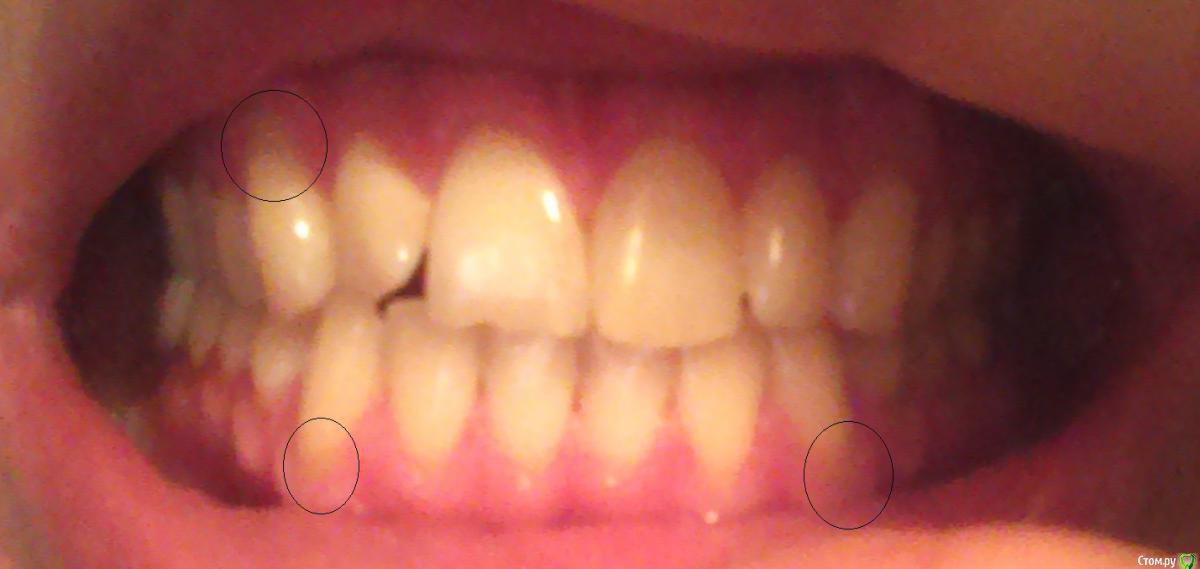

Bizzzin Опубликовано 7 декабря, 2015 Автор Поделиться Опубликовано 7 декабря, 2015 Конечно! В приложении направляю фотографии. Ссылка на комментарий

red_butler Опубликовано 8 декабря, 2015 Поделиться Опубликовано 8 декабря, 2015 Это рецессии десны, причина скорее всего в механической травме зубной щеткой. Закрываются они хирургическим путем. 3 Ссылка на комментарий